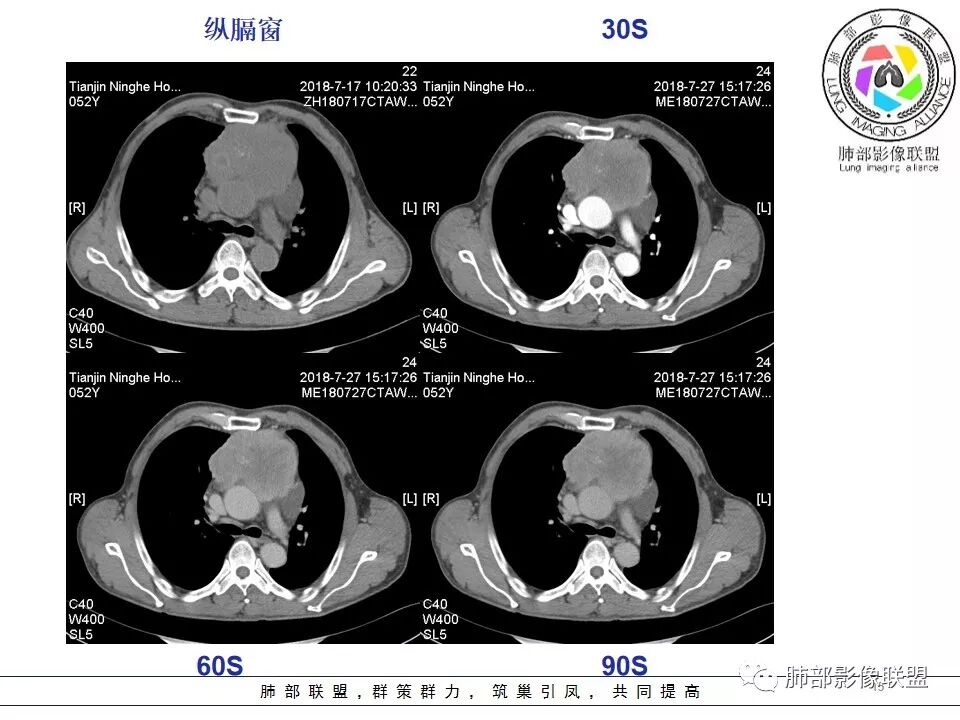

我们分析一下影像.

较大,内有囊变、钙化。

南边:边界大部分清楚,有些地方毛糙。

附近有淋巴结

南边:强化就不用说了

大肿块,边缘不清,伴随肿大淋巴结,上腔静脉受侵犯——恶性

侵袭性胸腺瘤?胸腺癌?老年,钙化、肿大淋巴结,边缘侵犯、累及心包、侵犯上腔静脉——支持